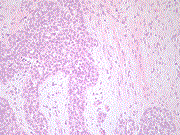

Fibroadenoma containing lobular carcinoma in situ, an unusual finding in a normally benign mass

Christie M Brock and others

Journal of Surgical Case Reports, Volume 2020, Issue 4, April 2020, rjaa059, https://doi.org/10.1093/jscr/rjaa059